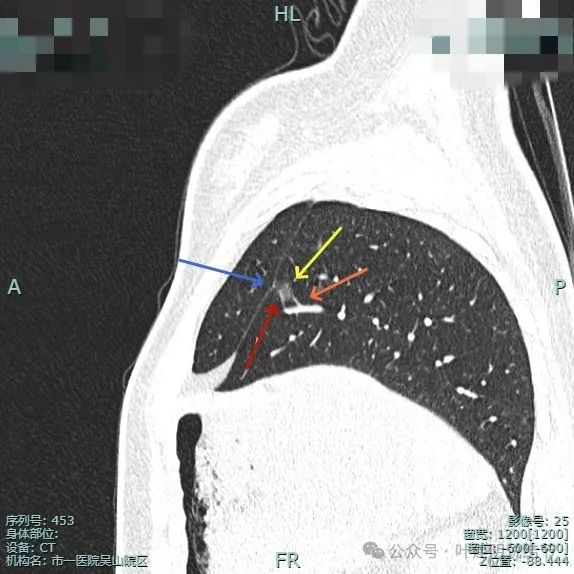

叶间胸膜牵拉较平扫上明显,血管进入也明显,整体轮廓清。

灶内有点状偏高密度成分,内部密度稍显杂乱;叶间胸腊牵拉,整体轮廓清。

多支血管进入,而且灶内的血管显得较病灶外略粗与略模糊,叶间胸膜牵拉是有的,力量不强。